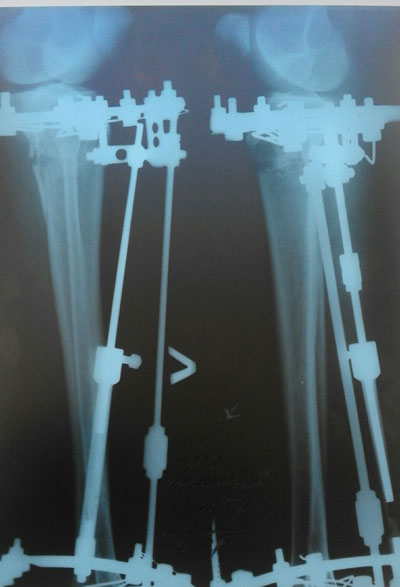

В процессе исправления деформации.